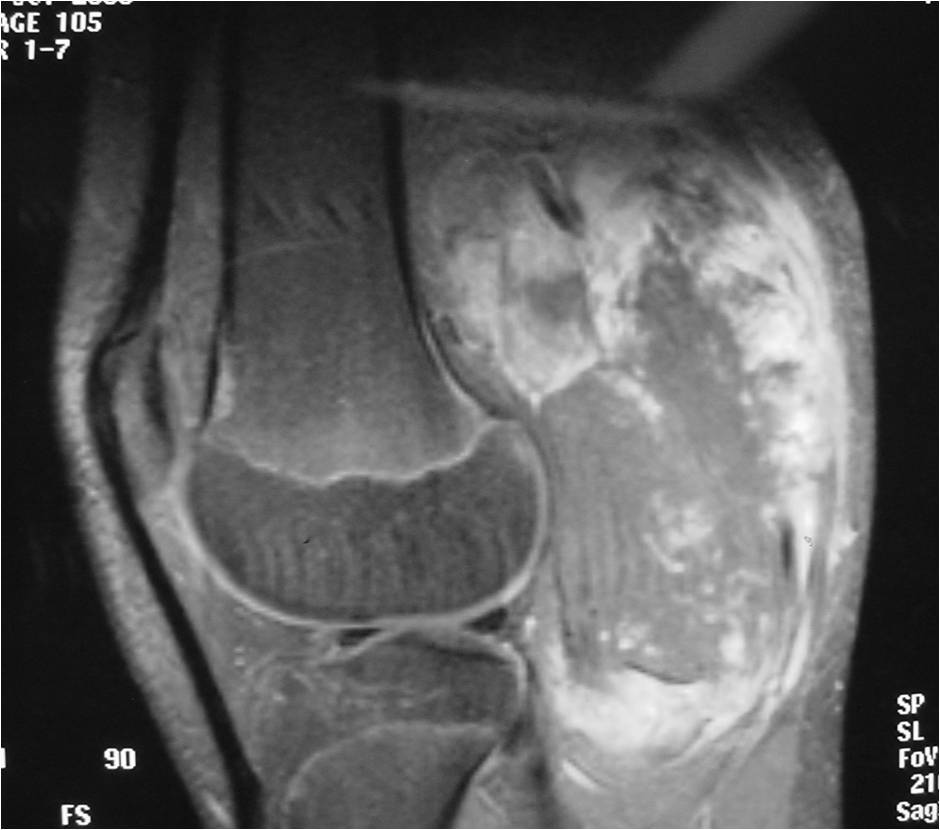

- Aggressive motheaten to permeative lesion

- Indistinct border in most cases

- Osseous destruction with a soft tissue component

- Chondroid matrix calcification may be present (60-70% of cases)

- Soft tissue mass

(Right Arrow) Cartilaginous Component